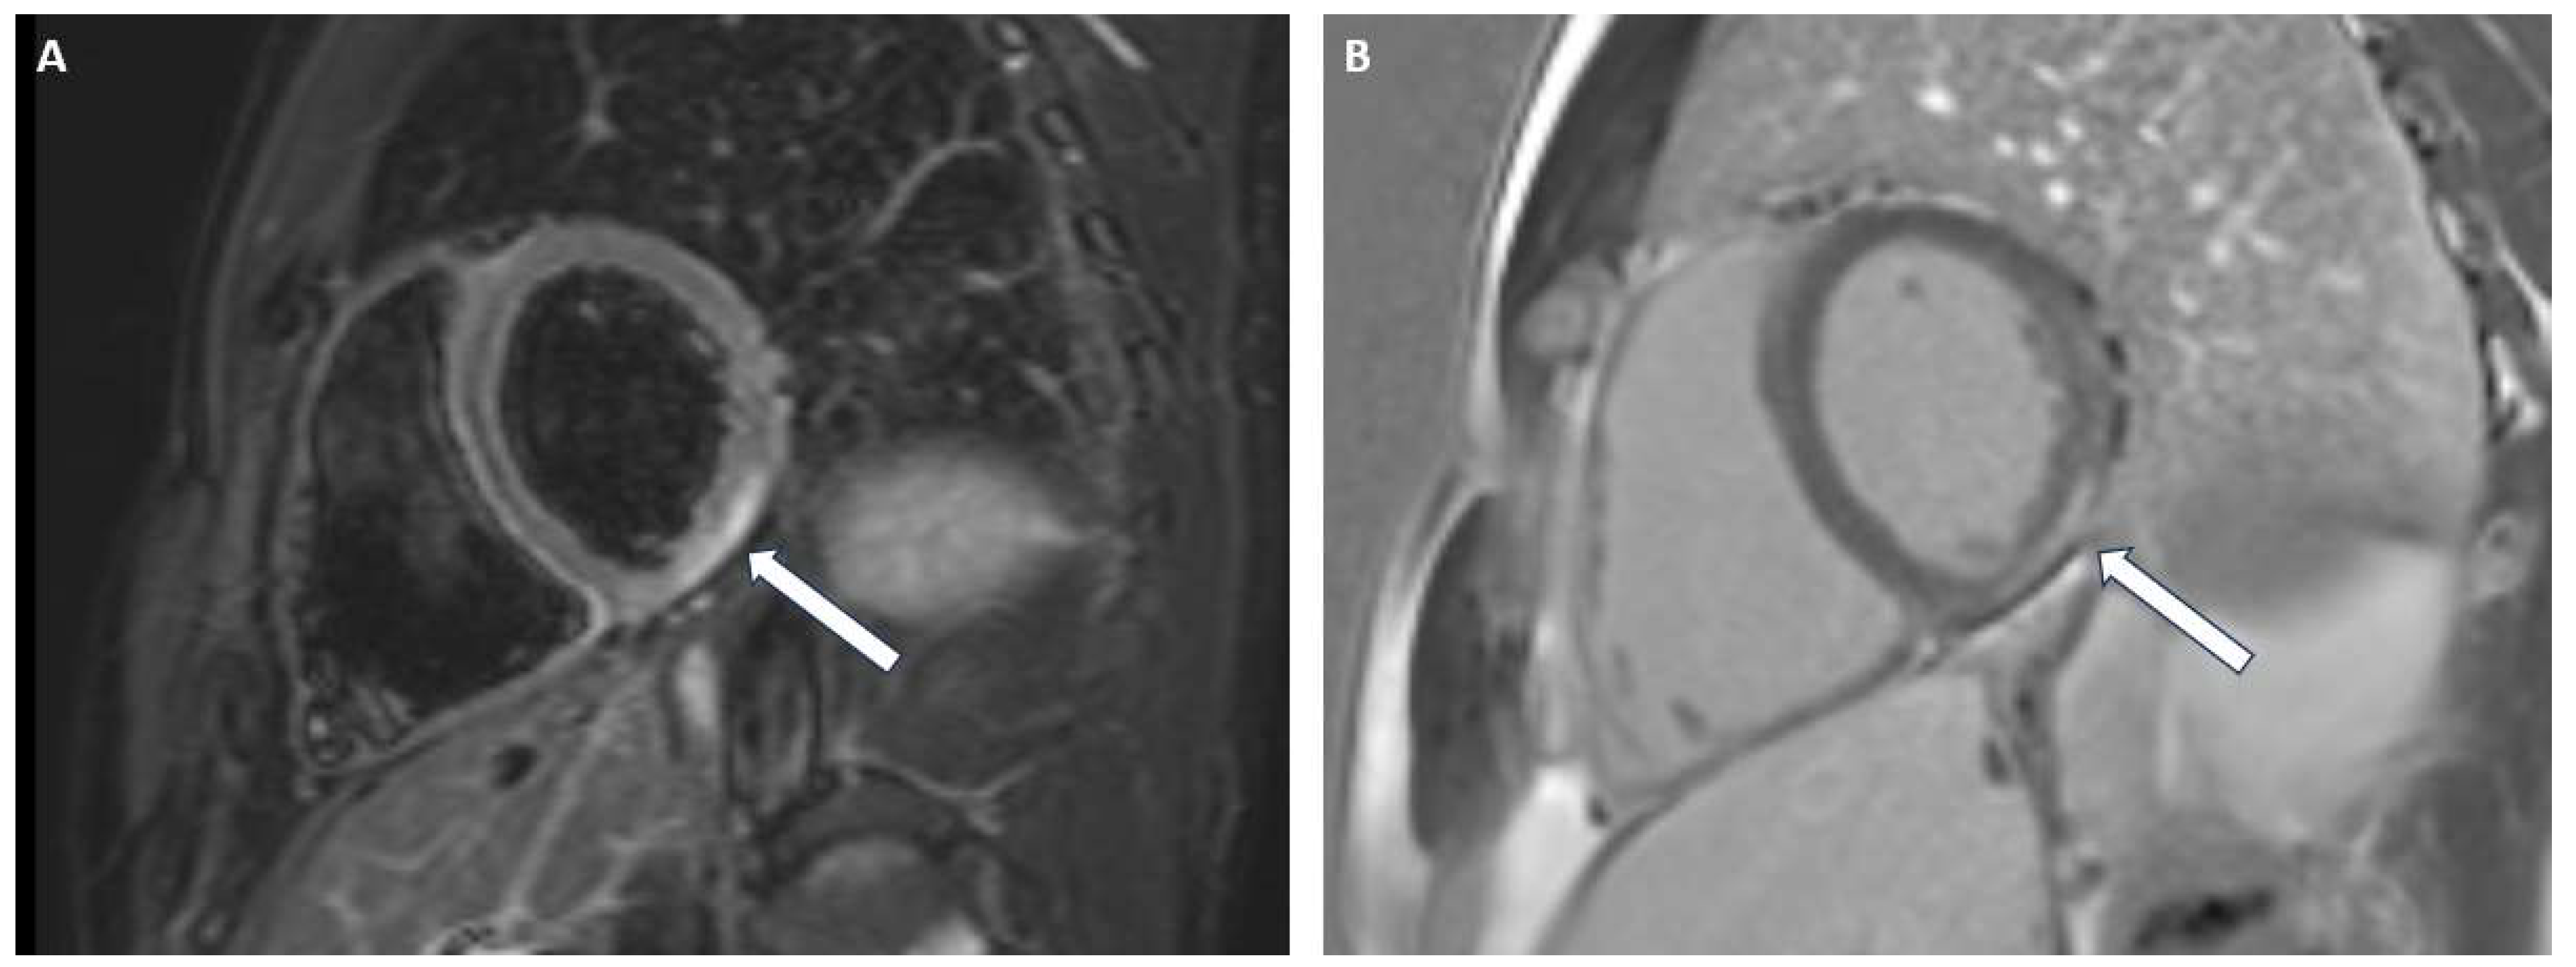

3.2. Acute Myocarditis